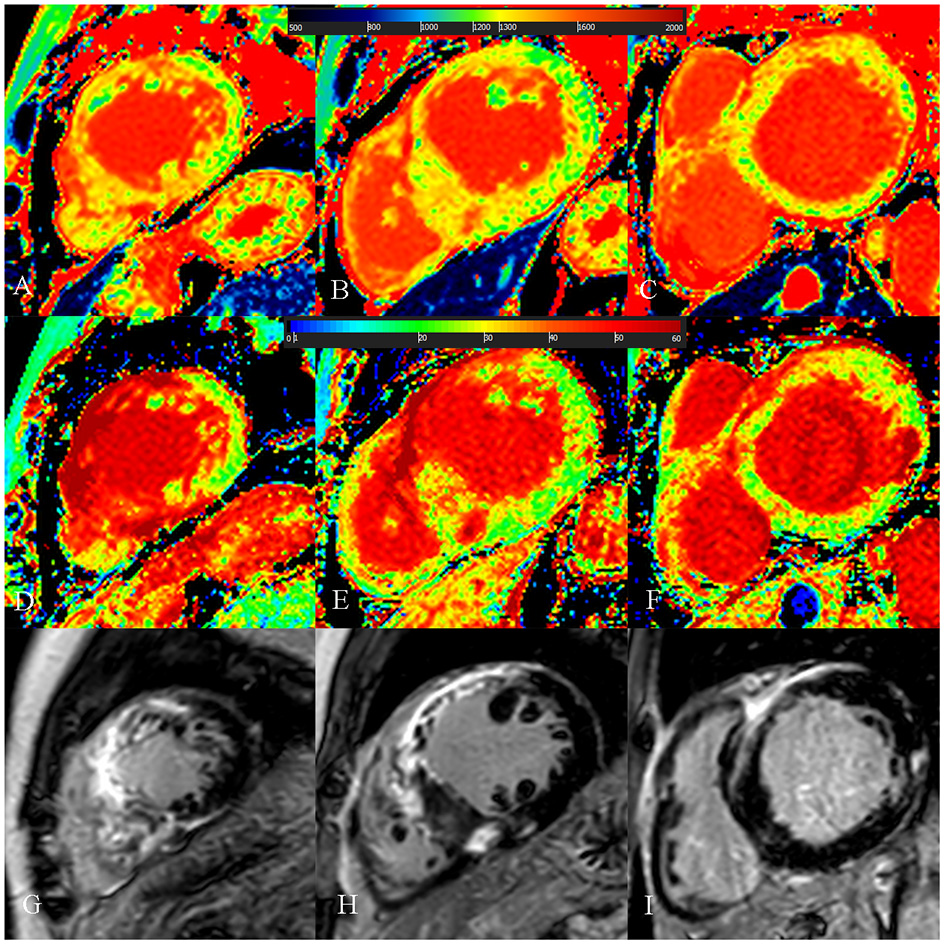

Figure 4

A 54-year-old male with diffuse septum hypertrophic cardiomyopathy. (A–C) Native T1 mapping of the apical, mid-, and basal portions of the left ventricular (LV) myocardium revealed higher global native T1 (1,359.67 ms). (D–F) Extracellular volume fraction (ECV) of the apical, mid-, and basal portions of the LV myocardium showed higher ECV (38.9%). (G–I) Late gadolinium enhancement (LGE) images of the apical, mid-, and basal portions of the LV myocardium showed multiple LGE. The maximal LV wall thickness was 24.3 mm, left atrial diameter was 55 mm, and the LV outflow tract gradient pressure was normal. He had non-sustained ventricular tachycardia but no family history of sudden cardiac death (SCD) and unexplained syncope. He had LGE/LV mass ≥15% (LGE/LV mass: 46.3%) and end-stage systolic dysfunction but no apical aneurysm. He was stratified as having high SCD risk under the 2014 European Society of Cardiology guidelines (5-year SCD probability: 5.93%) and enhanced American College of Cardiology/American Heart Association guidelines. He underwent the placement of ICD 6 months after cardiac MRI examinations. Higher global native T1 mapping and ECV values also indicated poor outcome.